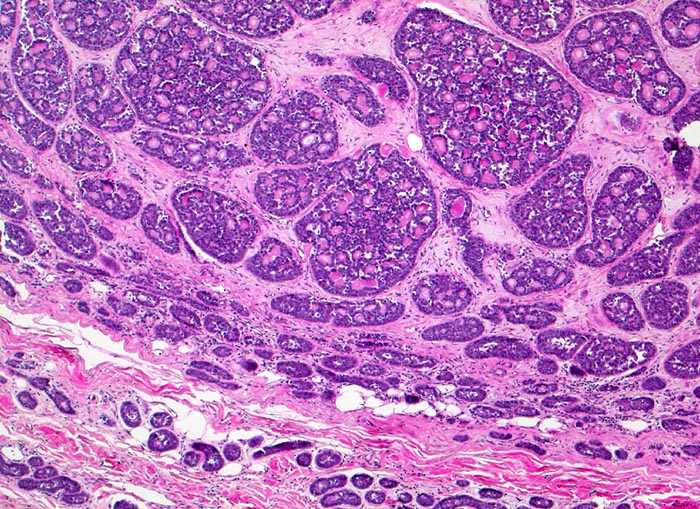

adenoidzystisches Karzinom der Glandula Parotis

Die einzelnen Tumorzellaggregate sind scharf begrenzt, teils solide und teils kribriform (siebartige Struktur). Die Hohlräume entsprechen nicht Drüsenlumina, sondern haben Kontakt zum Stroma, was besonders am Rand der kribriformen Strukturen erkennbar ist.

Schmerzhafter, rasch wachsender unscharf begrenzter Tumor in der Glandula Parotis.

Histologie

50